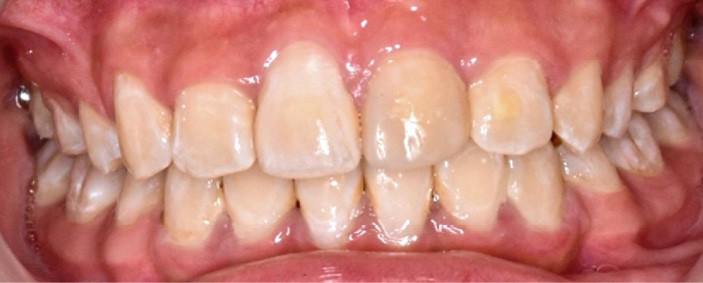

Par ailleurs, le rendu esthétique final du sourire reste marqué par une légère dyschromie entre les 11 et 21. Cela s’explique à la fois par la teinte plus saturée de la canine stratifiée, mais aussi par la discrète fluorose — visible en début de traitement sous forme de stries blanchâtres sur les incisives maxillaires et mandibulaires. De plus, l’apparition de white spot lesions secondaires au traitement a accentué le contraste chromatique. Un apport de vernis fluoré et une prise en charge par érosion-infiltration des lésions fluorotiques sont prévus afin d’harmoniser les teintes [4].

Enfin, une différence de hauteur gingivale est visible lors du sourire entre les collets de 21 et 11, mais surtout entre les 13 et 24. Un aménagement gingival pourra être proposé ultérieurement, selon les attentes esthétiques.